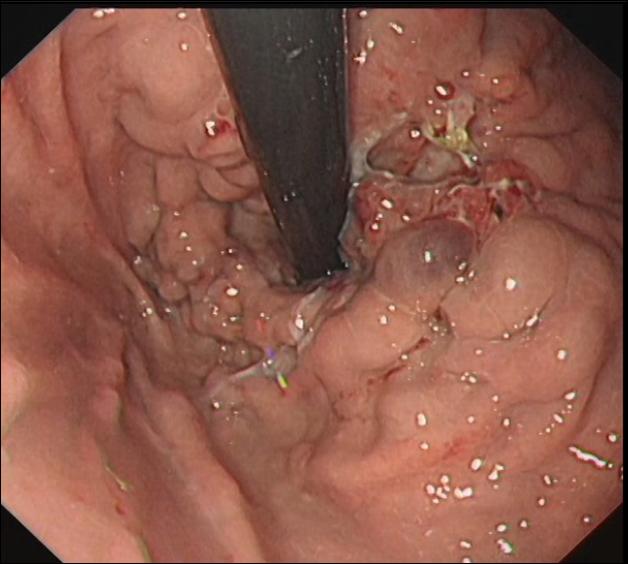

科室开展消化道早癌诊断技术、高难度食管异物取出技术、食管胃镜静脉曲张内镜下治疗、内镜逆行胰胆管造影术(ERCP术)、消化道息肉切除术、胆胰管狭窄扩张及支架植入术、内痔治疗等。

食管胃底静脉曲张破裂出血 内镜下曲张静脉结扎术后EVL

ERCP取石术 内镜下息肉切除